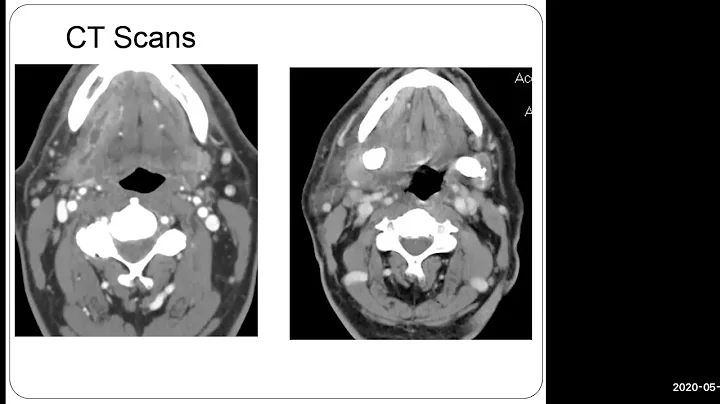

Salivary Endoscopy - Dr. Barry Schaitkin

May 4, 2020 Zoom Lecture entcovid.med.uky...